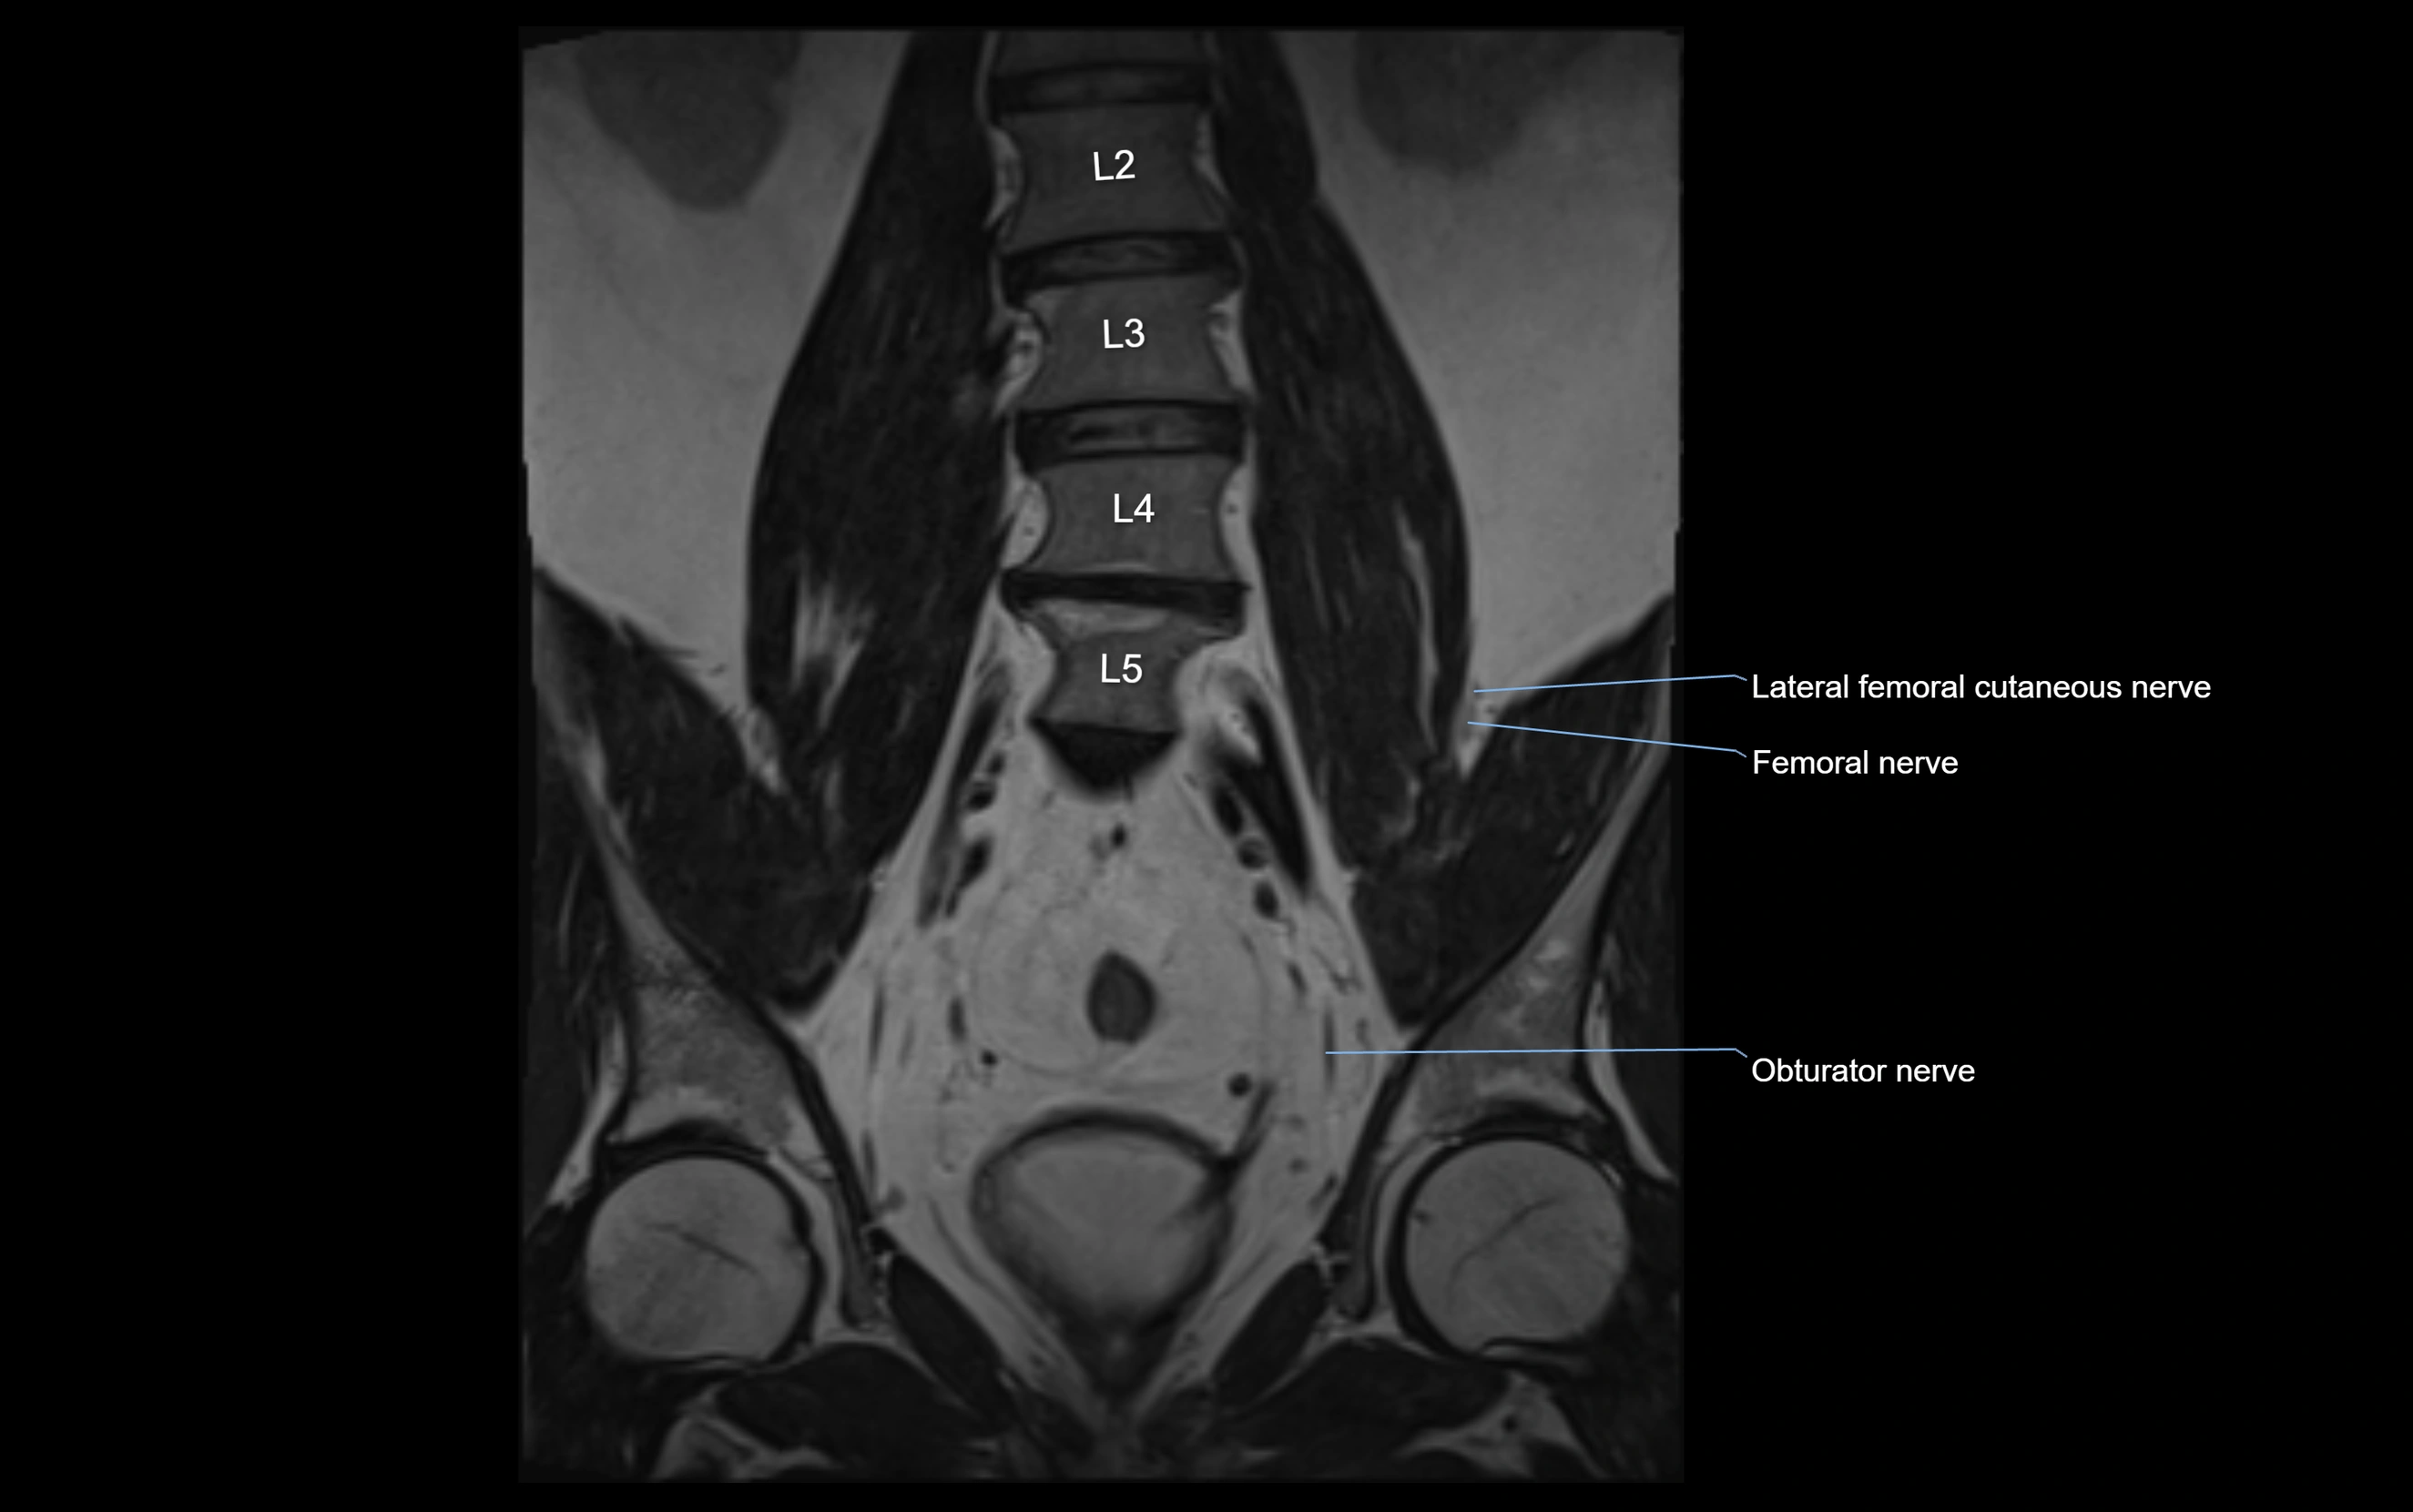

MRI image

image